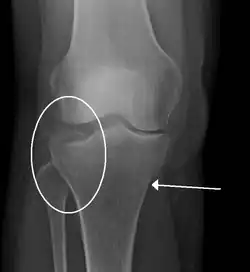

Lipohemarthrosis due to a tibial plateau fracture -

Subtle tibial plateau fracture on an AP X ray of the knee -

A tibial plateau fracture seen on X-ray